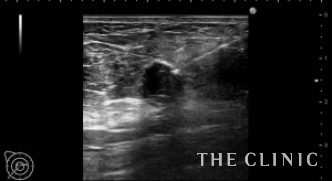

No.31でご紹介した方のオイルシストです。

右に13個・左に8個あり、それぞれ3㎜~15㎜の大きさです。

エコー下にて、穿刺吸引を行います。

全てのしこりを除去できました。